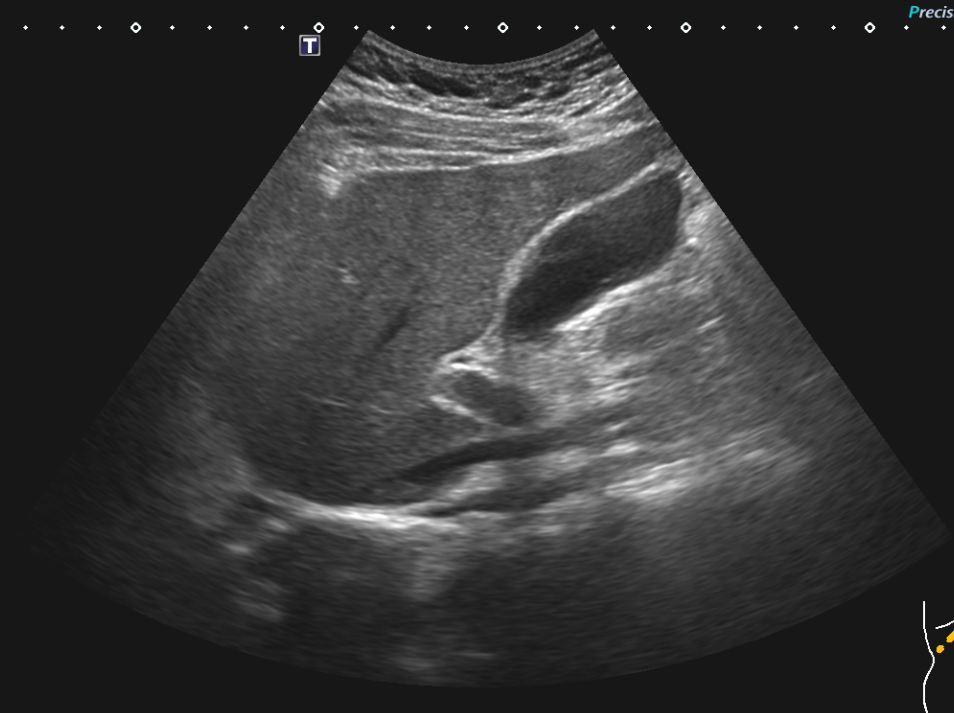

복부초음파 이부위가 오른쪽 상복부맞나요? 신장도 볼수있는자리인지

복부초음파 이 부위가 신장도 볼수있는 위치인가요? 오른쪽 상복부 맞죠?

신장에 단순 물혹 0.6cm가 mri 에서 보였는데 복부초음파에는 안보이는것같아서용

뭐가보이나요? 부위 사진 캡쳐하고 4장 같은부위 촬영사진 올려요

• 1번 째 사진

맨 위 사진의 위치에서는 probe를 tilting을 하면 신장이 보이기는 하지만

그 보다는 신장의 관찰을 위해서 probe를 조금더 아래 level로 가지고 갑니다.